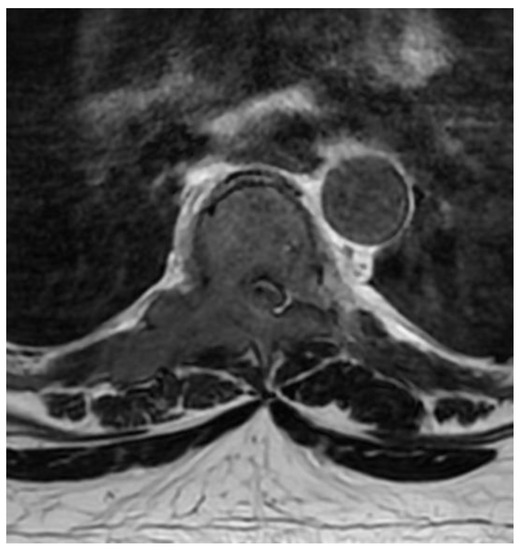

Fully Endoscopic Spine Separation Surgery in Metastatic Disease—Case Series, Technical Notes, and Preliminary Findings

2. Materials and Methods

3. Results